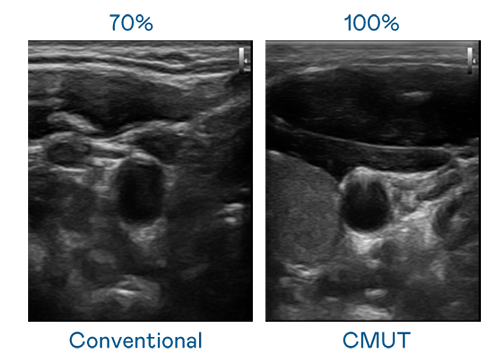

CMUT 技术是一种用电容式微机电元件来产生超音波讯号的技术。与传统 PZT 压电式技术相比,CMUT 频宽增加 30%,更宽频的超音波讯号让影像解析度大幅提升,是实现高影像品质医疗超音波扫描、促进精准医疗发展的关键技术。

超音波影像的解析度高低,首先取决于探头能发出的讯号频宽。绿巨人在线观看免费高清视频在线观看下载 CMUT 可提供高清晰的超音波讯号,提供高频宽、高灵敏度、影像纹理细节更高的超音波影像,协助医护人员缩短影像判读时间及利用精准的医疗影像进行诊断。